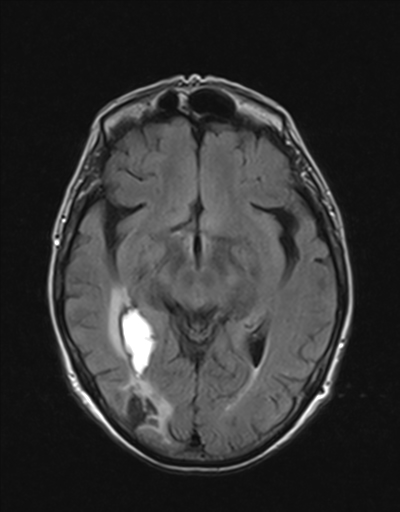

Prueba diagnóstica no invasiva que consiste en la obtención de imágenes de alta definición anatómica de las órbitas mediante el empleo de un campo electromagnético y ondas de radio (con un emisor y un receptor). No utiliza radiación ionizante. Indicaciones: visión doble, traumatismo, sospecha de tumor, hipertiroidismo.